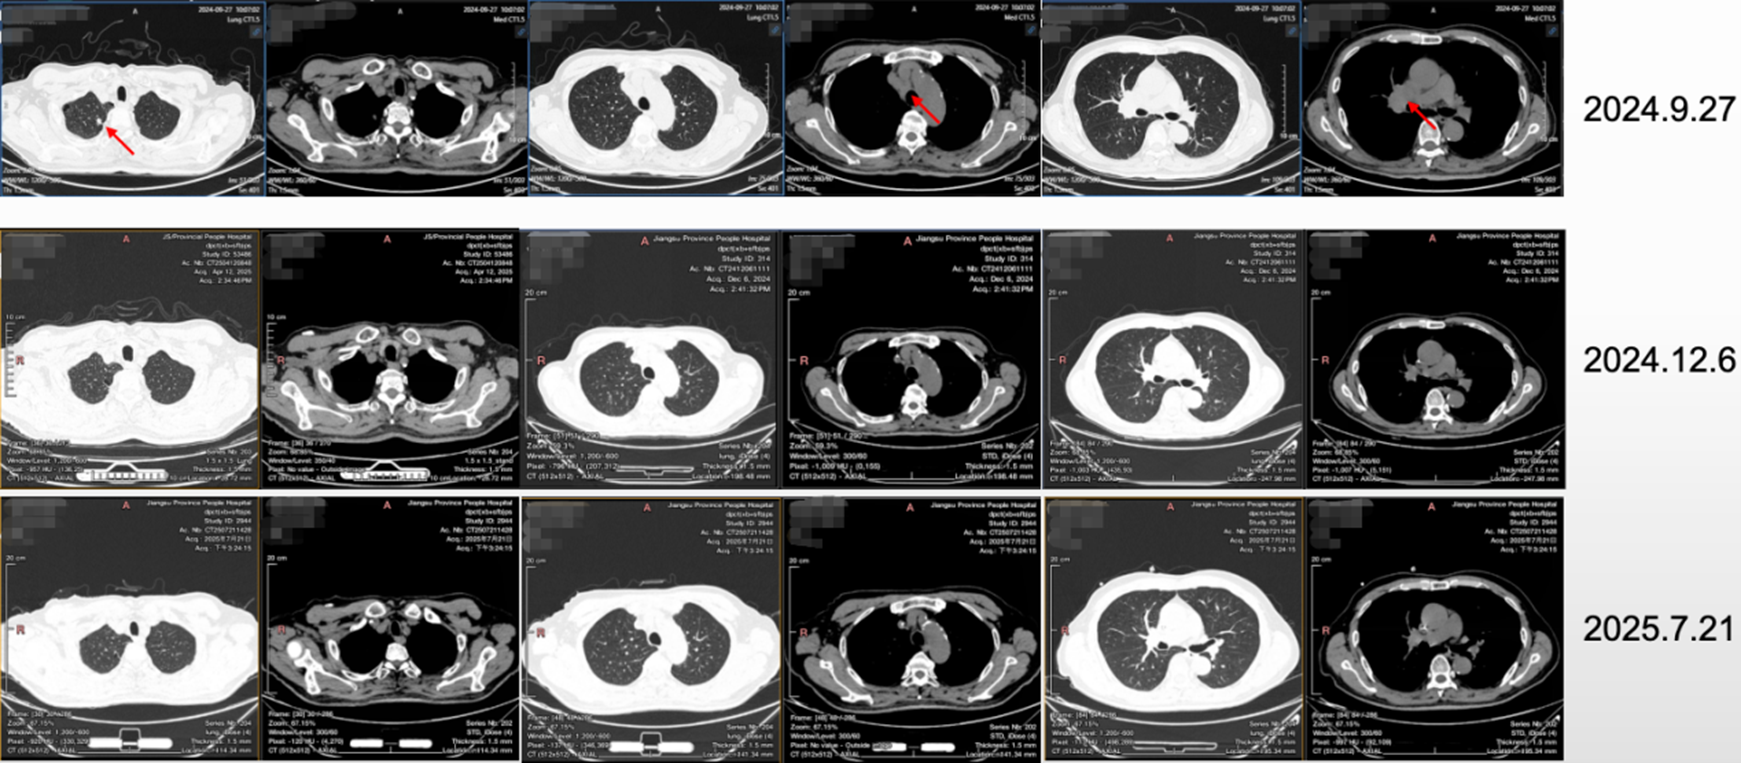

• 治疗2周期后,2024.12.6复查CT,达部分缓解(PR)。

图2 治疗2周期后复查CT结果

• 后持续规律治疗及随访,复查CT结果显示,病灶持续缓解。

图3 治疗11周期后复查CT结果

该患者因“体检发现右上肺占位伴纵隔淋巴结肿大半月余”入院,综合辅助检查后,诊断为右肺SMARCA4缺失型低分化癌IVB期(cT1bN3M1C,多发骨转移),驱动基因阴性,STK11及KEAP1双突变,PD-L1 TPS=1%,PS评分0分。考虑传统免疫联合化疗方案在此类患者中疗效有限,“靶免一体”创新机制药物可能会为患者带来更好的疗效,经综合评估,2024年10月15日起,一线治疗选择了6周期依沃西单抗联合化疗方案,后使用依沃西单抗单药维持治疗。治疗2周期后病灶迅速缓解,疗效评估达PR,目前仍持续治疗中,截止最新随访时间(2025.11.06),PFS已超过1年。